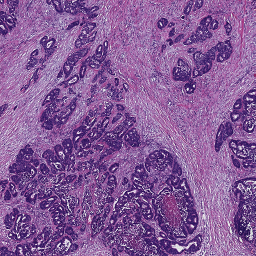

3.2 The importance of stain normalization

The definition of classes in our RC data is slightly different from the one coming with the CRC dataset. Therefore, we grouped corresponding classes as described in Table 2, which resulted in a 6-class problem, used to evaluate the performance of the trained ConvNet applied to CRC data. Applying the ConvNet directly to CRC data gave a poor accuracy value of 50.96% (experiment A). Based on this result, we investigated the role of staining in this classification task. For this purpose, we selected a representative RC image from the RC cohort as the template image to define the mapping parameters for the SN1 and SN2 algorithms999The function for SN1 is available in the form of look-up table at https://github.com/francescociompi/stain-normalization-isbi-2017. Successively, we stain-normalized patches in the CRC dataset and classified it again with the same ConvNet. Stain normalization allowed to remarkably improve the accuracy by more than 20%, reaching values of 75.55% (experiment B) and 73.99% accuracy for SN1 and SN2 respectively. Besides the difference in accuracy, we found that SN2 failed to normalize 3 patches of adipose tissue, and it tends to force color normalization regardless of the type of tissue considered. As an example, in Figure 4, two CRC patches are depicted, containing tumor and blood cells respectively. While both SN1 and SN2 correctly normalize stain for the tumor patch, the characteristic red color of blood cells is completely lost using SN2, while SN1 keeps a substantial component of the red channel.

Based on the positive result of the previous experiment, the question remains whether stain normalization should only be applied to test data or also to training data. To address this question, we introduced SN1 in our training and testing pipeline and evaluated the accuracy of a ConvNet trained on RC data and applied to CRC data in four different configurations, namely with (experiment C) and without (experiment D) stain normalization applied to RC (training) data and to CRC (test) data. The results are reported in Table 3, where for the sake of clarity a letter is assigned to the result of each combination. As expected, experiment D resulted in the lowest performance, since the ConvNet does not learn any stain variability from the training set, while such a variability is expected in the test set. Although all the training cases come from the same cohort and staining was done in the same lab, experiment C gave an improvement of 5% accuracy compared to B, which indicates that the ConvNet can benefit from the variability in the training set. It is worth noting that experimental settings of A represents what is commonly done in digital pathology research, where training data from a given cohort, with some variability are used to train a classifier, whose performance are evaluated on an independent set of data coming from different laboratories and stained with different procedures. Experiment B reduced the variability in the test set by adapting data to match the stain distribution of the template image. Finally, experiment C showed a substantial improvement compared to all other possible combinations of settings. Qualitative results of images in CRCt classified under the settings of experiment C are depicted in Figure 5.